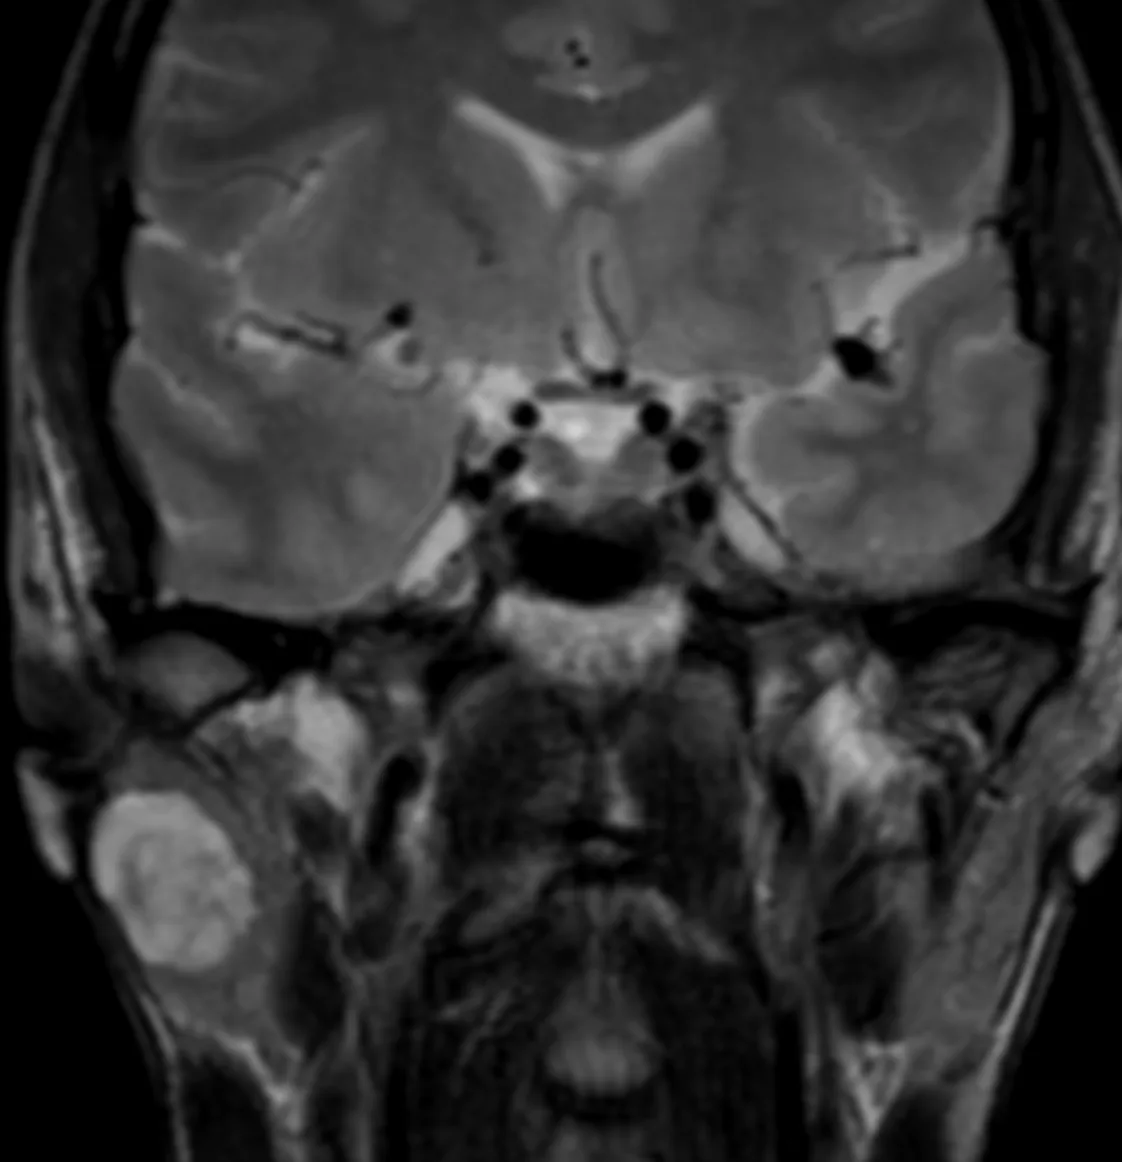

Менингиомы иногда не ходят одни. А по две, три и больше. Самая крупная слева в ЗЧЯ - хорошо видно место, из которого она растет: фокальные утолщения кости по краям и плоское основание опухоли (стрелки).